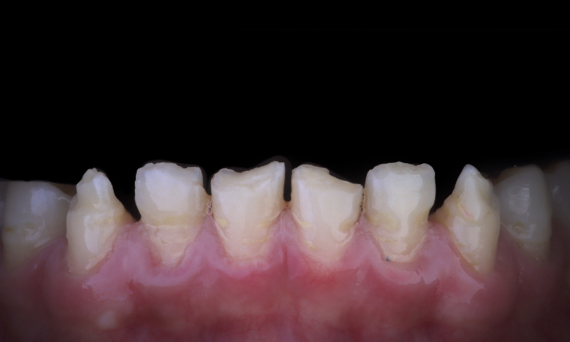

Full mouth rehabilitation with 28 all-ceramic restorations

A particular and protracted case of skeletal Class II malocclusion and generalized amelogenesis imperfecta in a teenager was referred for prosthetic rehabilitation. The aim of the treatment was to prepare the remaining tooth structure, remove undercuts, and make room for all-ceramic crowns covering the entire dentine and simulating the lost enamel.

Before: Initial situation prior to orthodontic treatment.